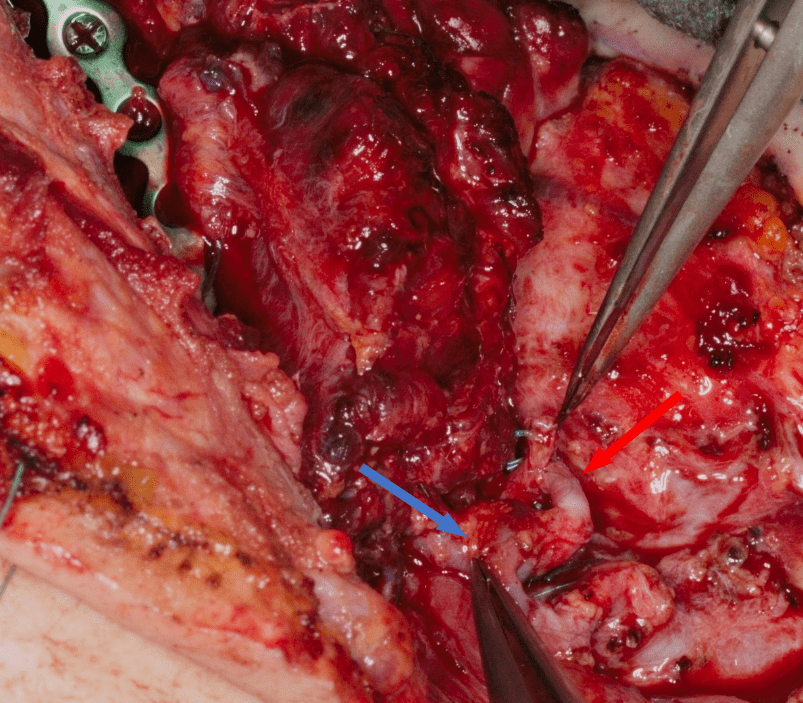

Jednoczasowo wypreparowano wolny płat mikronaczyniowy z prawego talerza biodrowego oparty na naczyniach okalających biodro głębokich (DCIAF), wycinając go z kolcem biodrowym przednim górnym w kształcie litery L o wymiarach 3 cm x 6 cm przy użyciu wcześniej przygotowanego szablonu chirurgicznego indywidualnego, odwzorowującego wiernie zresekowany fragment żuchwy (Fig. 11., 12.). Przed odcięciem szypuły płata do części grzebienia biodrowego odtwarzającego trzon żuchwy wprowadzono 3 implanty firmy Alpha Bio MultiNeo CS średnicy 4,2 mm i długości 10mm przy użyciu szablonu chirurgicznego, uzyskując ich stabilizację pierwotną (Fig. 13., 14., 15., 16., 17.). Po przygotowaniu do mikrozespoleń naczyń okalających biodro głębokich Fig. 18.), płat mikrochirurgiczny przeniesiono w miejsce zresekowanej żuchwy i unieruchomiono minipłytką rekonstrukcyjną tytanową dogiętą na modelu stereolitograficznym uzyskując pełną jego stabilizację (Fig. 19). Następnie zespolono tętnicę okalającą biodro głęboką z tętnicą twarzową prawą, uzyskując prawidłową reperfuzję płata zarówno w części kostnej jak i w mięśniach oraz wypływ krwi żylnej z żyły okalającej biodro głębokiej, którą zespolono z prawą żyłą twarzową (Fig.20.).

Fig. 20. Wykonane mikroanastomozy tętnicza (strzałka czerwona) oraz żylna (strzałka niebieska)